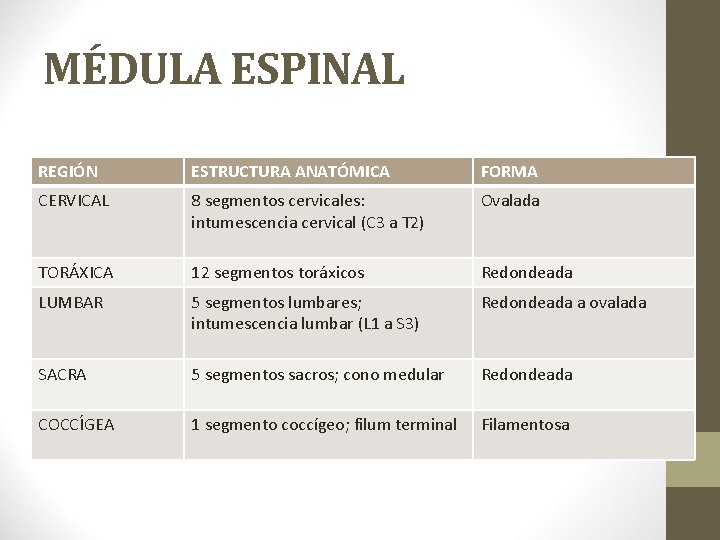

MÉDULA ESPINAL REGIÓN ESTRUCTURA ANATÓMICA FORMA CERVICAL 8 segmentos cervicales: intumescencia cervical (C 3 a T 2) Ovalada TORÁXICA 12 segmentos toráxicos Redondeada LUMBAR 5 segmentos lumbares; intumescencia lumbar (L 1 a S 3) Redondeada a ovalada SACRA 5 segmentos sacros; cono medular Redondeada COCCÍGEA 1 segmento coccígeo; filum terminal Filamentosa